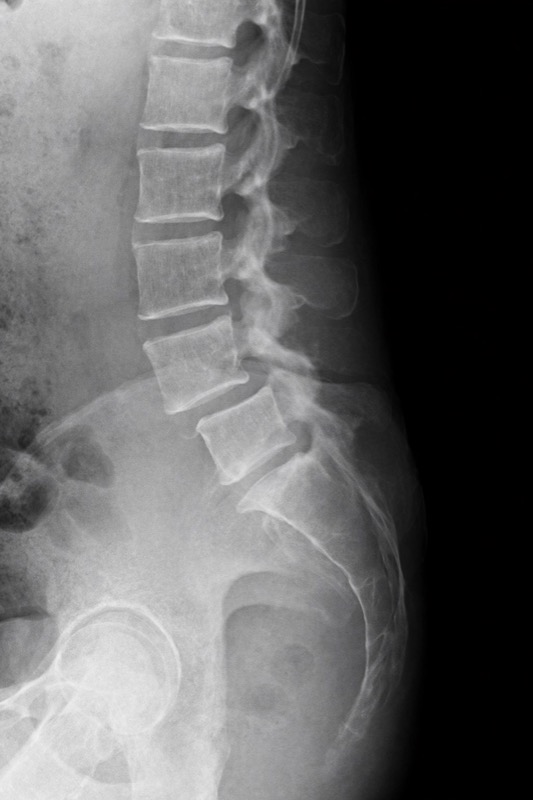

La espondilolistesis causa dolor lumbar e irradiado a piernas. Conoce los tipos, síntomas y técnicas de cirugía mínimamente invasiva disponibles en Santiago.